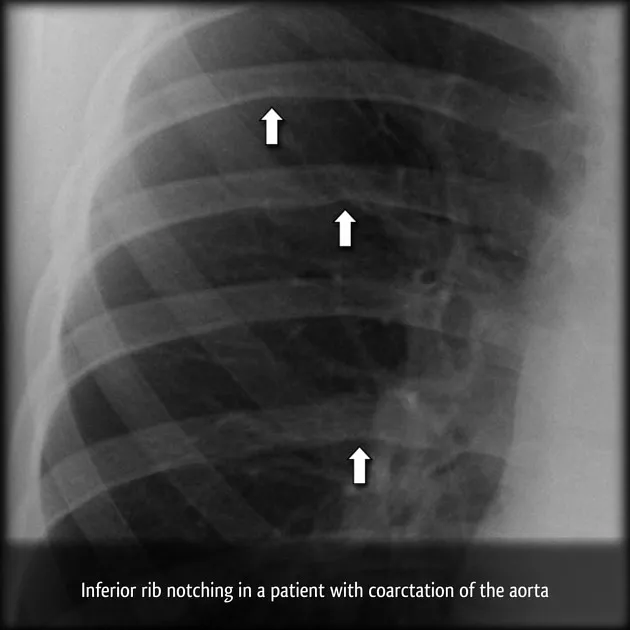

- Coarctation of the Aorta: Localized aortic narrowing, typically near the ductus arteriosus.

- Presents with ā upper extremity BP, ā lower extremity BP.

- Classic sign: Brachial-femoral pulse delay.

- Associated with Turner syndrome and bicuspid aortic valves.

ā Look for rib notching on chest X-ray in coarctation, caused by intercostal artery enlargement from collateral circulation.